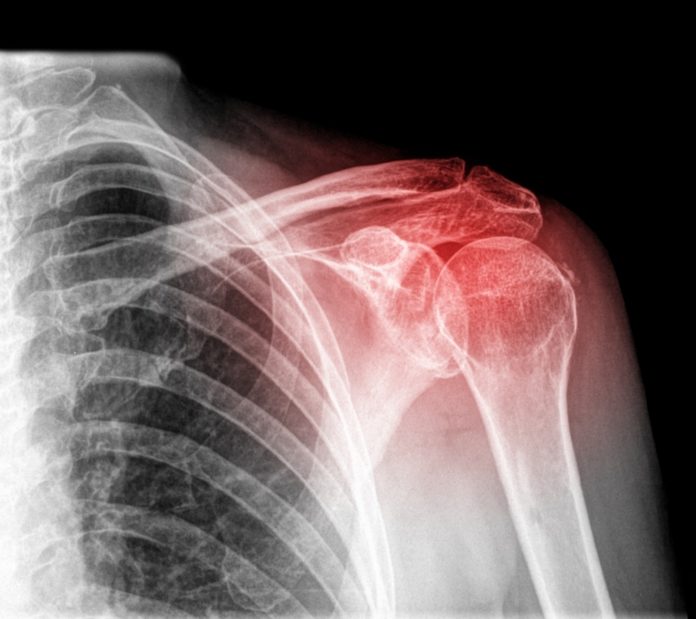

Εκφράζουμε εκ νέου την ανησυχία μας για την παρούσα κατάσταση, η οποία μπορεί να προκαλέσει σημαντικές επιπλοκές στους ασθενείς. Επισημαίνουμε δε, ότι τα άτομα με ρευματικά νοσήματα, εξαιτίας της φύσης των συγκεκριμένων νοσημάτων, συχνά ταλαιπωρούνται εξαιρετικά μέχρι να βρεθεί μια συμβατή και αποτελεσματική θεραπεία, η οποία να επιτρέπει ικανοποιητική ποιότητα ζωής. Όταν αυτός ο στόχος επιτευχθεί, η εξασφάλιση αυτής της θεραπείας, σε τακτική βάση, είναι ουσιώδους σημασίας για την εξέλιξη του νοσήματος, την πρόληψη της αναπηρίας και την διευκόλυνση της ψυχοκοινωνικής τους κατάστασης, σε μια περίοδο εξαιρετικά πιεστική εξαιτίας της οικονομικής δυσχέρειας.